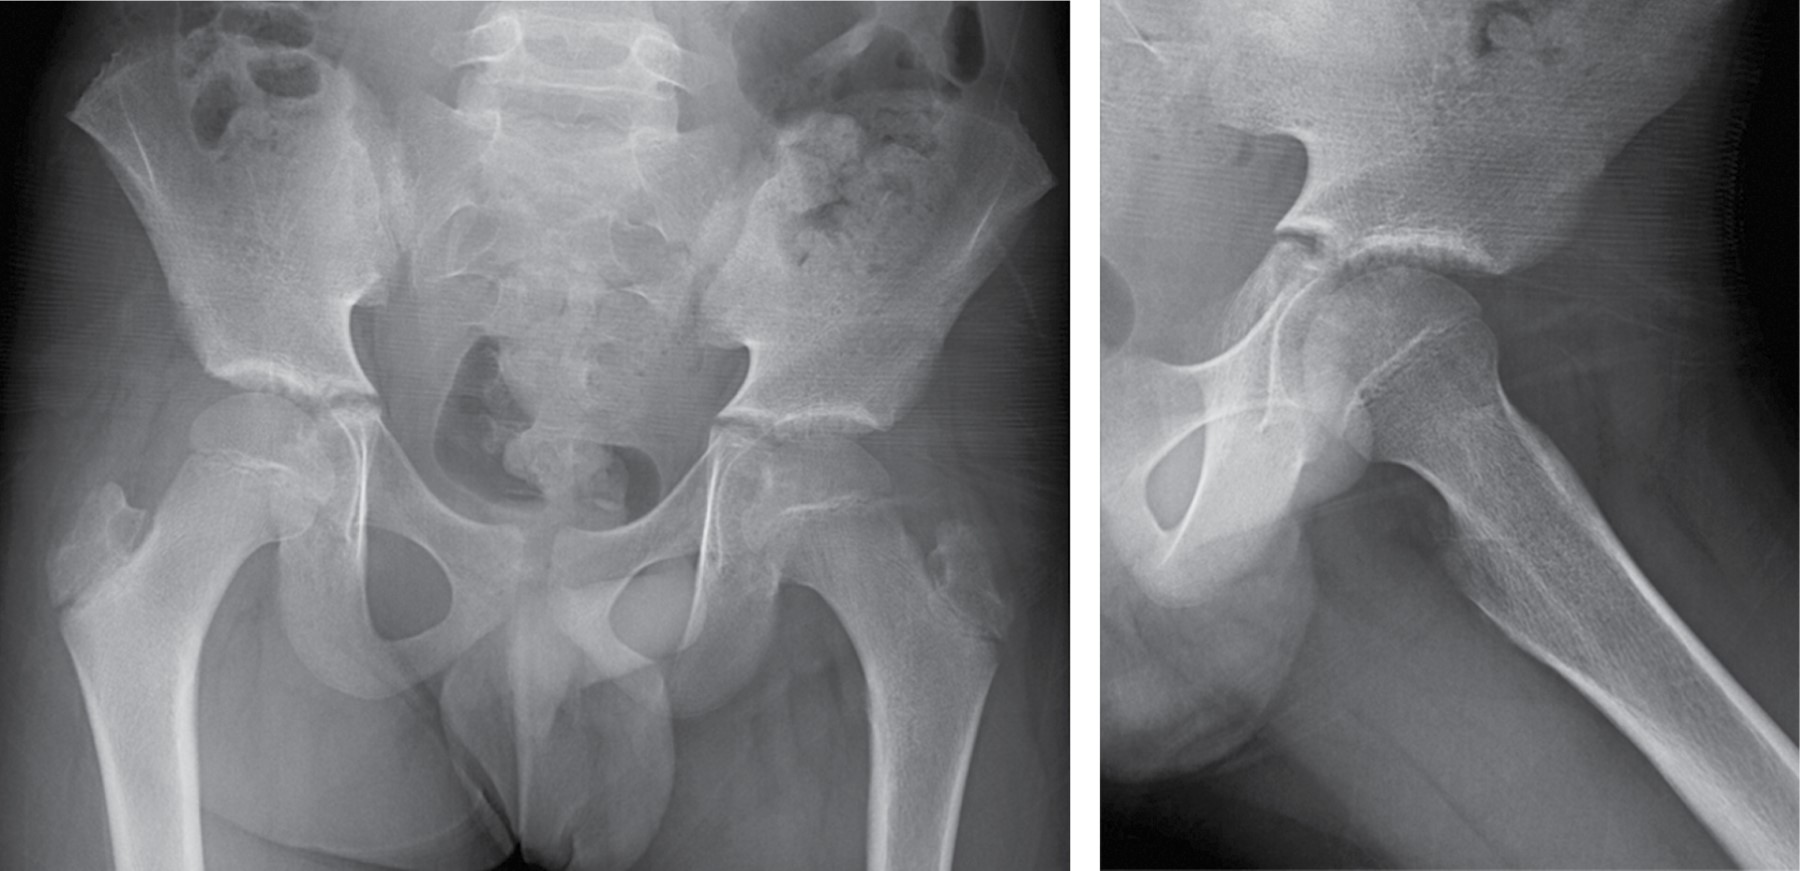

Transient synovitis after COVID-19

During the recent COVID-19 world pandemic, we report the case of a 12-year-old patient referred to our hospital with hip pain and limping who had been diagnosed with COVID-19 two weeks before. Altogether, normal X-ray and laboratory findings, alongside an ultrasound compatible with synovitis let us diagnose transient synovitis. The patient was treated with anti-inflammatory drugs and rest, with satisfactory evolution. Conclusions: Coronavirus led to a proinflammatory situation which might be cause of atypical symptoms. We described one of the first cases of post SARS-CoV-2 transient synovitis. However, more studies are needed to stablish causal relationship.

Figure 1